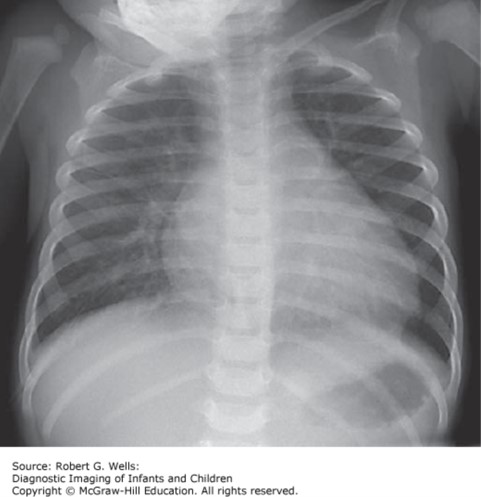

She has had a nonproductive cough for the last 2 weeks. She denies any rhinorrhea, sneezing, or recent sick contacts. She is afebrile. Her heart rate is 122 bpm, her respiratory rate is 38 breaths per minute. On exam, she has a grade III/VI holosystolic murmur. Her chest X-ray shows cardiomegaly with clear lung fields.

The correct answer is “C.” Although tachycardia, tachypnea, a holosystolic murmur, and cardiomegaly can be consistent with a VSD, this presentation is unlikely to be seen in a 15-year-old. Primary cardiomyopathies are the most likely cause of heart failure in people with structurally normal hearts. Given that the patient is 15 years old, it is unlikely that she has unrecognized significant congenital heart disease, especially if she has been cared for in developed nations. Dilated cardiomyopathy is due to a genetic mutation in sarcomeric, cytoskeletal, or cell membrane proteins. This leads to systolic heart failure and dilation of the ventricles. The murmur heard on exam is due to mitral regurgitation that results from the ventricular dilation and poor function.